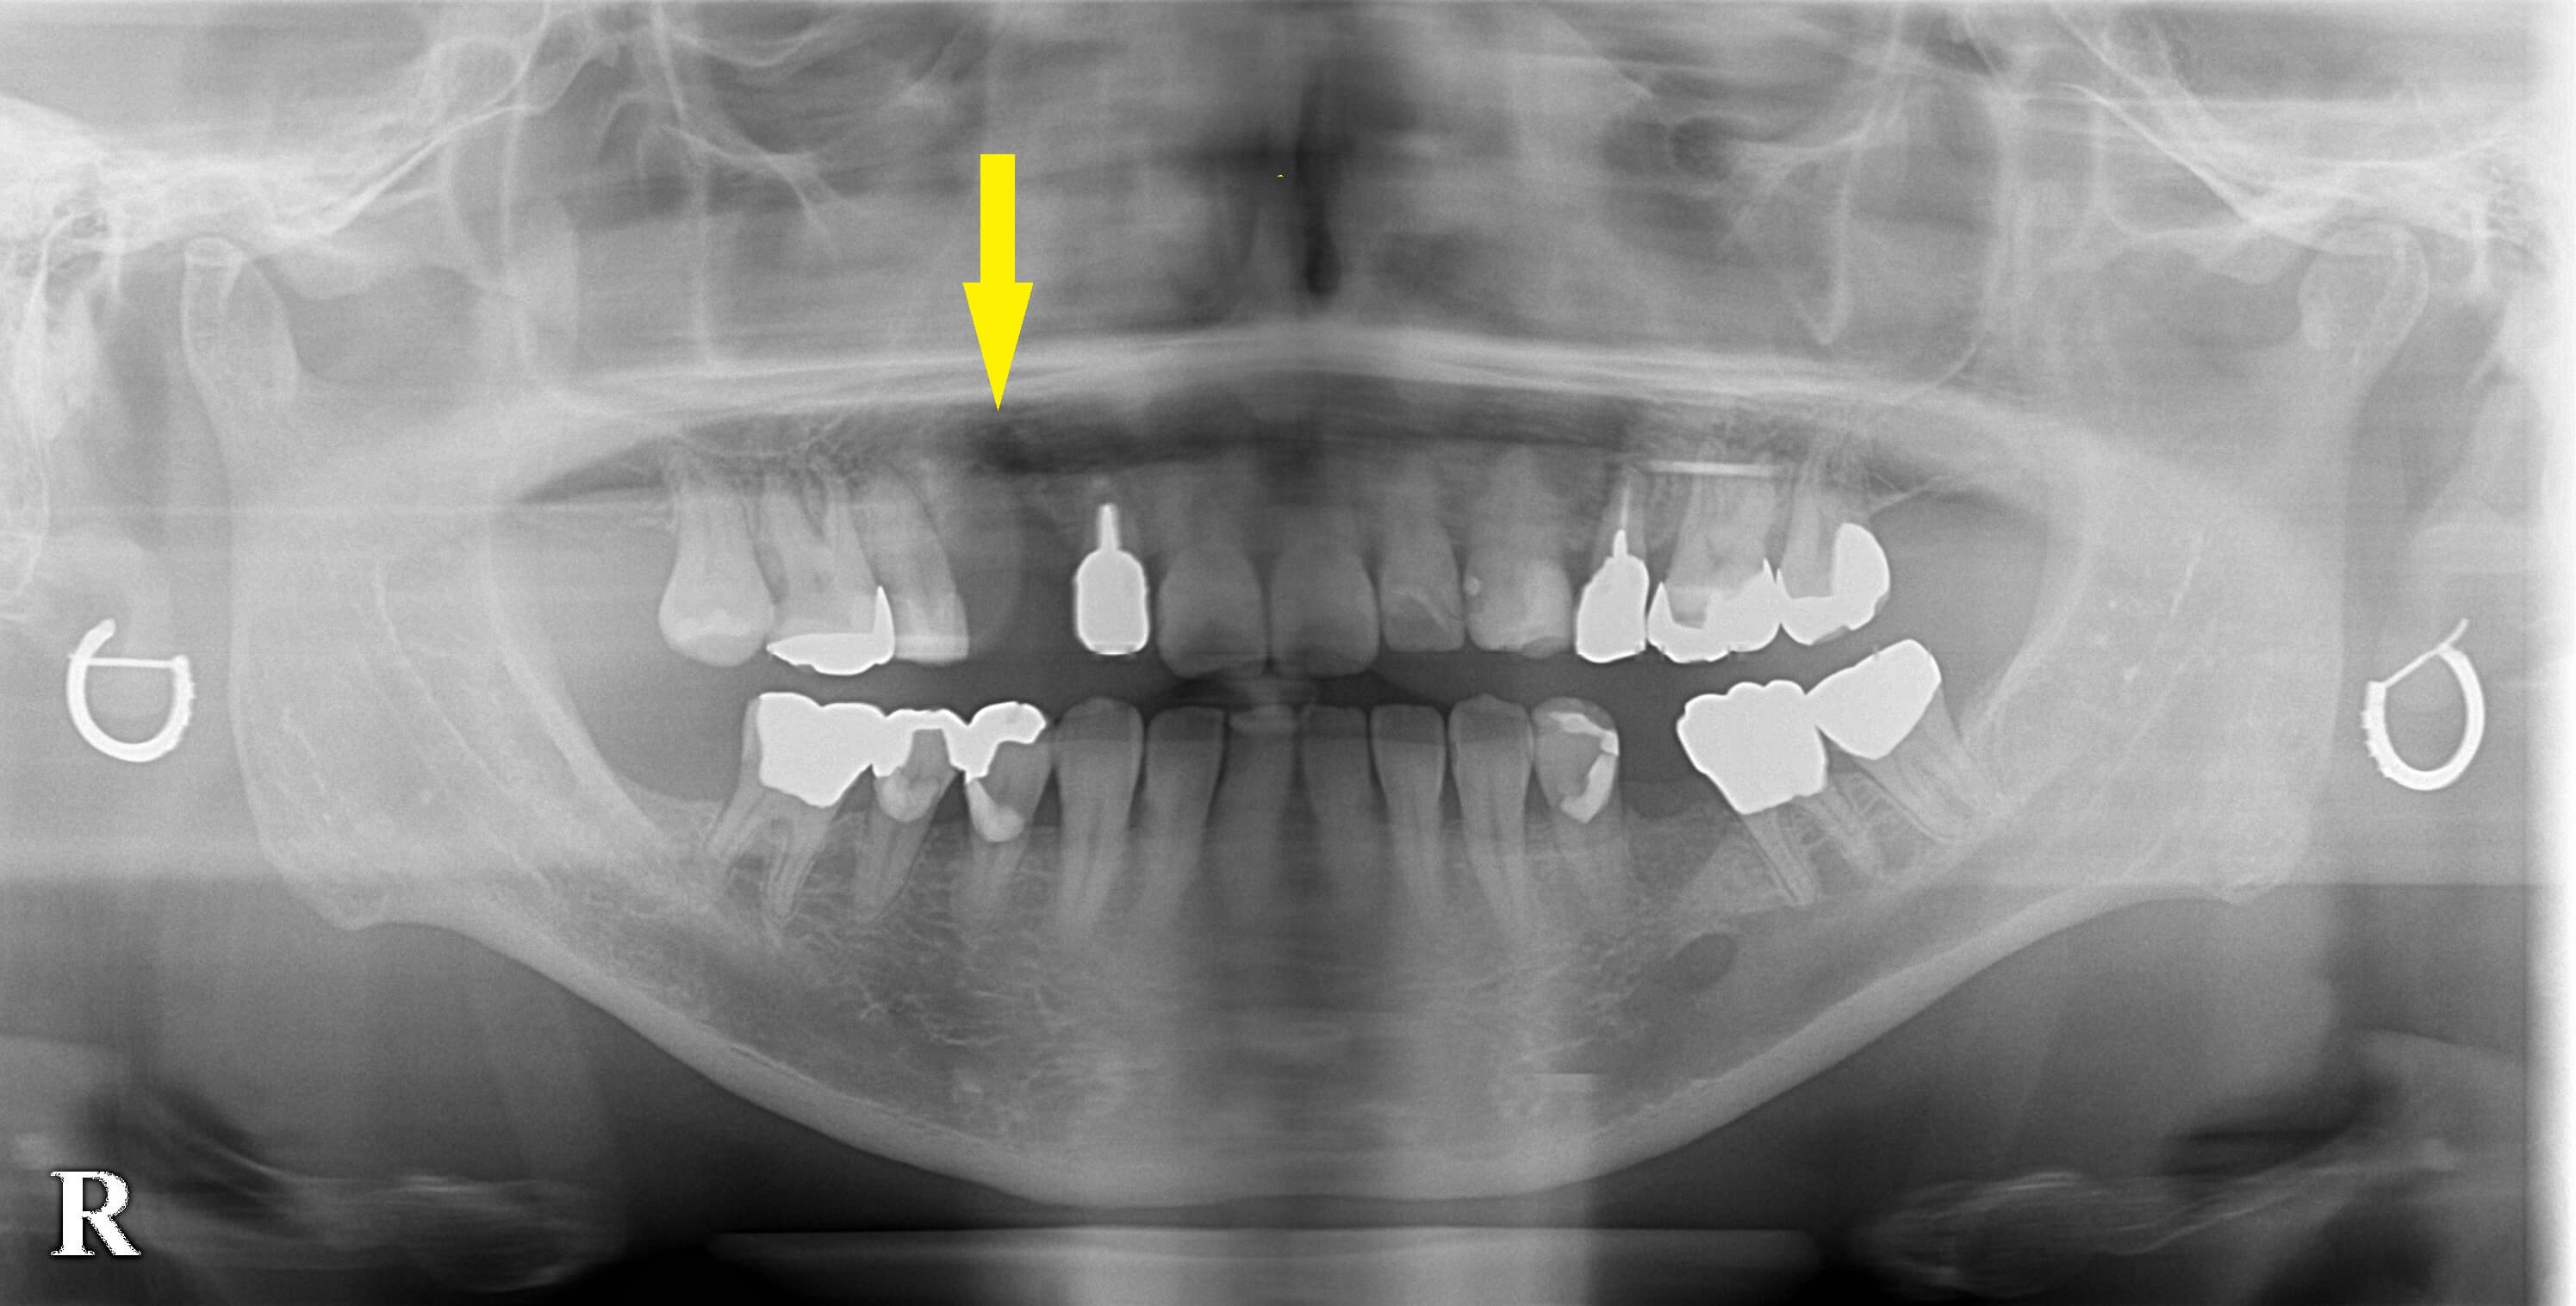

CTを見ると、やはり骨の厚みが不足しており、直径が3~4mmあるインプラントを通常通りには埋入できません。

そこで、インプラント埋入と同時に、外側に人工骨を補填して骨幅を増やす造成術を併用する方法で行うこととしました。

下段の写真左が手術前のCT、右が手術後のCTです。

薄かった骨にインプラントが埋入され、外側(写真でインプラント体の左側)に白く写る人工骨を認めます。